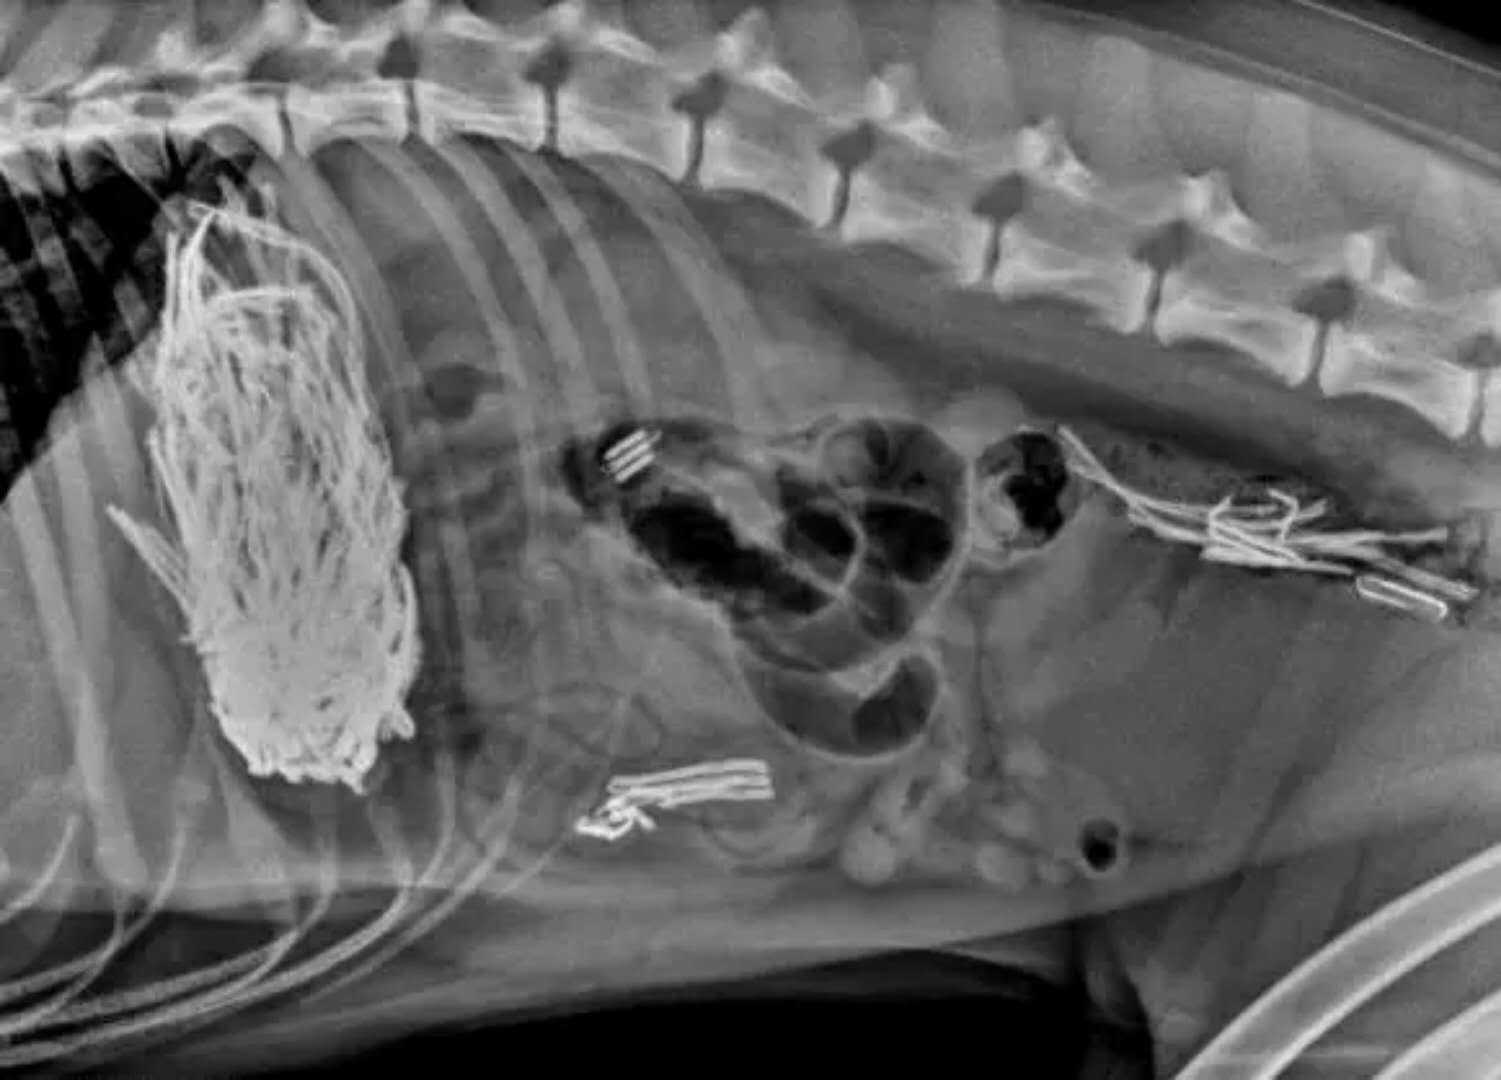

这是在狗狗胃里发现的勺子

这些都是在狗狗的胃里发现的,拍的X光图,看到那把刀在狗狗胃里,心里不紧张吗不担心 ,万一你家的狗狗也吃下去,想都不敢想!

狗狗似乎总是无法控制自己去吃一些没有营养价值的东西。针线、木勺、硬果壳、果核、塑料袋、珠宝、石块、抹布和袜子都有可能吃下去,狗狗胃内长期滞留这些异物不能被胃液消化,会造成胃黏膜损伤,影响胃功能。